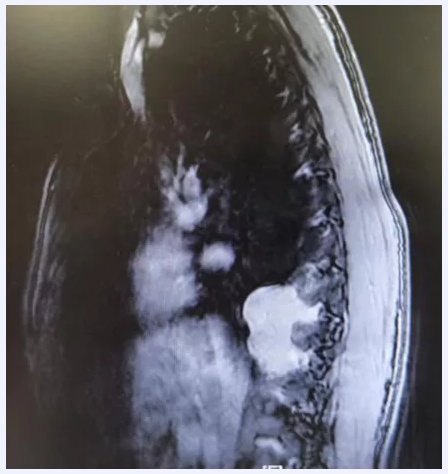

这种肿瘤“脾气”很“臭”——手术刀刚“挨”上它,它就让患者的血压一路飙升;一旦切掉它,它又会“遥控”患者的血压一路暴跌,危及生命,被称为“手术中的隐形杀手”。不久前,经过多学科反复会诊和一个月的术前准备,在北京天坛医院的手术室里,手术医生和麻醉医生一起,联手与这样一个罕见地长在胸腔的异位嗜铬细胞瘤展开“斗智斗勇”的较量。

患者有高血压、糖尿病病史,在手术时循环出现剧烈波动,金旭怀疑,这位患者很可能患有内分泌功能副神经节瘤(异位嗜铬细胞瘤)。“这种肿瘤发病数量本身就不多,发病多在肾上腺或腹部,长在胸腔的非常罕见。”金旭说,如果准备不充分,这种肿瘤手术死亡率非常高,堪称手术中的“隐形杀手”。医院胸外科主任魏博和麻醉科主任韩如泉立即对这名患者情况进行联合会诊,一致认为继续手术患者死亡可能性较大,经过充分与患者家属沟通,决定暂停手术,积极进行术前准备。

随后,北京天坛医院胸外科、麻醉科、泌尿外科、内分泌科等多学科专家针对这位患者的病情进行会诊,确定这位患者所患的就是异位嗜铬细胞瘤。“对于麻醉医生来说,这是一次巨大的考验。”金旭介绍,“手术中对肿瘤的刺激会导致血浆中去甲肾上腺素和肾上腺素急剧升高,引起高血压、严重心动过速或过缓、快速性心律失常等,随时威胁患者生命;术后人体失去了肿瘤分泌的大剂量去甲肾上腺素‘支持’,很可能出现循环坍塌,出现顽固性低血压,而这种‘坍塌’对外源性的去甲肾上腺素不敏感,换句话说,药物很可能效果不好。”